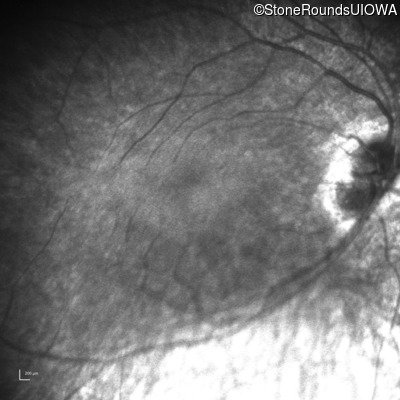

SECORD (IA2b)

Age at visit:

27 years

OD

OS

Light Perception

SECORD

RPGRIP1

His631Arg CAC>CGC

Pro237 del1ccA

AR